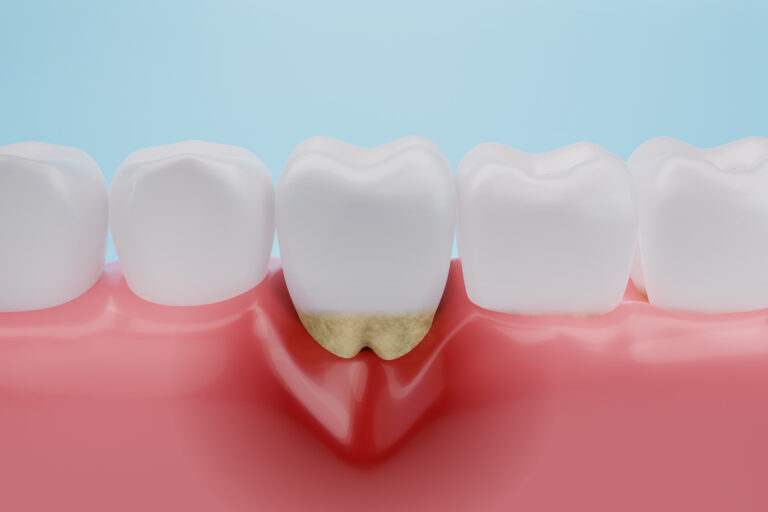

Leczenie kanałowe jest jedną z najczęściej wykonywanych procedur w gabinetach stomatologicznych. Procedura ta polega na usunięciu zakażonej lub uszkodzonej miazgi z wnętrza zęba, a następnie wypełnieniu powstałej przestrzeni specjalnym materiałem. Leczenie kanałowe pozwala uratować ząb, który w przeciwnym razie musiałby…